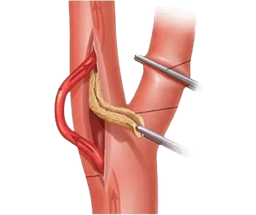

Carotid Endarterectomy

A carotid endarterectomy is a surgical procedure that involves the treatment of carotid artery disease. The carotid arteries, in fact, are one of the main blood vessels that transfer oxygen and blood to the brain. When these arteries become narrowed, it reduces the blood flow to the brain, which can eventually lead to a stroke. -br During a carotid endarterectomy, using a surgical approach, the surgeon removes plaque that has formed inside the carotid artery. This is done by making an incision on the side of the neck over the affected carotid artery. After opening the artery, the plaque is carefully removed. Once the plaque is removed, the artery is stitched back as before. This procedure helps restore the normal flow of blood to the brain. -br It is important to note that this procedure is performed under general anesthesia, although the patient is not completely in a sleep state.